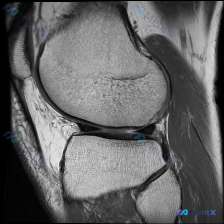

看到这个有意思的病例,整理了完整的影像资料和分析思路分享给大家。 病例核心信息 临床提示:可疑半月板异常,提供单张膝关节矢状位T1加权MRI影像 影像系统分析 先给大家整理一下这张影像的客观所见: 1. 图像质量:标准矢状位T1WI序列,信噪比良好,解剖结构显示清晰,无明显运动伪影 2. 骨骼结构:...